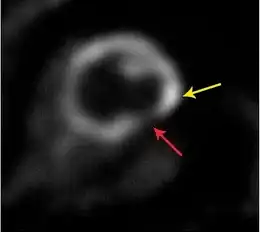

In cardiology, hibernating myocardium is a state when some segments of the myocardium exhibit abnormalities of contractile function.[1] These abnormalities can be visualised with echocardiography, cardiac magnetic resonance imaging (CMR), nuclear medicine (PET) or ventriculography. Echocardiography: A wall motion abnormality at rest which improves during a low-dose dobutamine stress test is classified as "hibernating myocardium." Low dose dobutamine stimulates contractile function and thus helps to predict functional recovery after revascularization. Cardiac magnetic resonance: The most frequently used MR contrast agents based on Gd-chelates accumulate in the extracellular space which is increased in scarred myocardium. This leads to a signal increase which can be visualised with the "late gadolinium enhancement technique." This is probably the most accurate way to visualise scarred myocardium. An alternative (or additional) technique with CMR is the use of low dose dobutamine similar to echocardiography. PET: The finding of a perfusion or metabolic mismatch between PET-FDG and PET-NH3 is indicative of decreased metabolism. The wall of the affected segments is hypo-, a-, or dyskinetic.